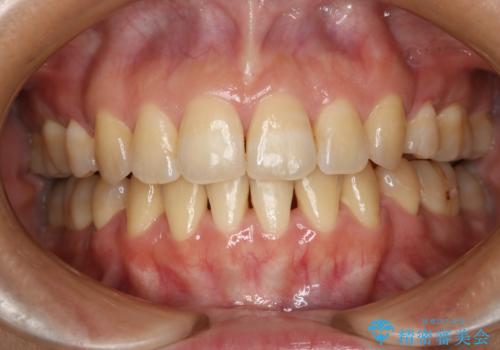

[マウスピース矯正] がたがたの歯並びをきれいにしたい

![[マウスピース矯正] がたがたの歯並びをきれいにしたいの症例 治療前](https://seimitsushinbi.jp/wp/wp-content/uploads/2025/06/0d238550c8a0fddc4de7b2c337c6c786-500x350.jpg?v=1750323380)

![[マウスピース矯正] がたがたの歯並びをきれいにしたいの症例 治療後](https://seimitsushinbi.jp/wp/wp-content/uploads/2025/06/IMG_0002-2-500x350.jpg?v=1750323305)